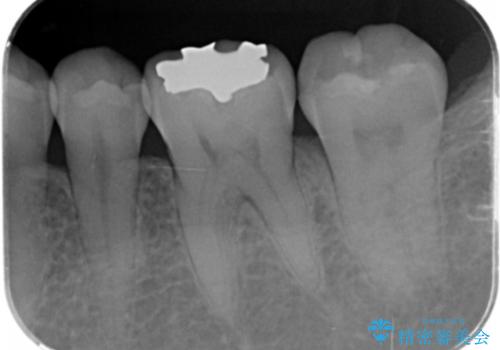

- 笑った時に見える銀歯を無くしたい、虫歯治療をしたい。とセラミック治療を希望され来院されました。

銀歯の除去・虫歯の除去を行ったのち、適合の良い精密なジルコニアセラミッククラウンを製作します。